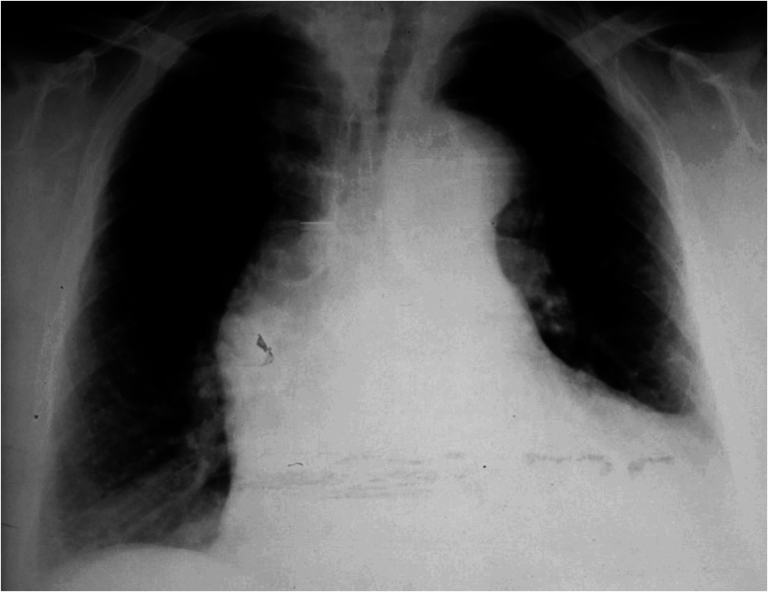

Severe chest recession causing translucency on an x ray ADC Fetal Definition Of Chest Recession Recession is a clinical sign of respiratory distress which occurs as increasingly negative intrathoracic pressures cause indrawing of part. They're still trying to get air into your lungs, but the lack of air pressure causes the skin and soft tissue in your chest wall to sink in. The movement is most often a sign that. These movements are known as. Definition Of Chest Recession.